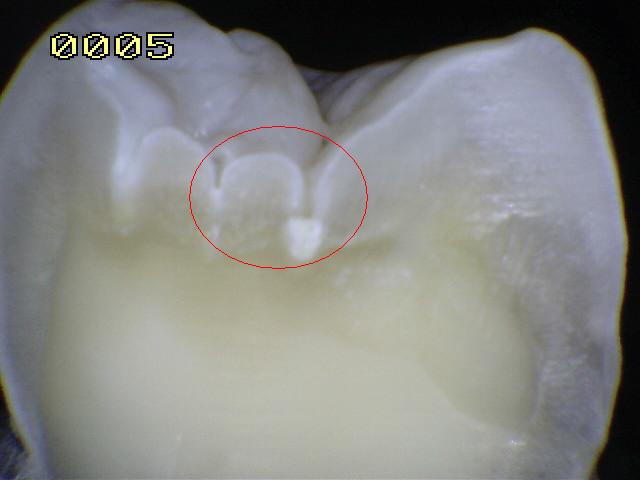

Código 2:

Lesión de caries observada en esmalte en estado húmedo y

permanece después de secar

- Al observar el

diente en estado húmedo verá una decoloración (mancha blanca

/ marrón)

en el fondo de la fosa y fisura y que desborda hacia las

paredes. (mas ancha que la fosa y fisura) las manchas

no tienen brillo y es consistente con desmineralización.